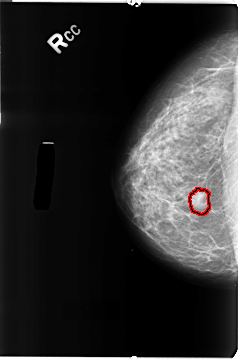

B_3132_1.RIGHT_CC

RIGHT_CC LINES 4664 PIXELS_PER_LINE 3104 BITS_PER_PIXEL 12 RESOLUTION 50 OVERLAY

FILE: B_3132_1.RIGHT_CC.OVERLAY

TOTAL_ABNORMALITIES 1

ABNORMALITY 1

LESION_TYPE MASS SHAPE LOBULATED MARGINS CIRCUMSCRIBED-ILL_DEFINED

ASSESSMENT 4

SUBTLETY 4

PATHOLOGY BENIGN

TOTAL_OUTLINES 1

BOUNDARY